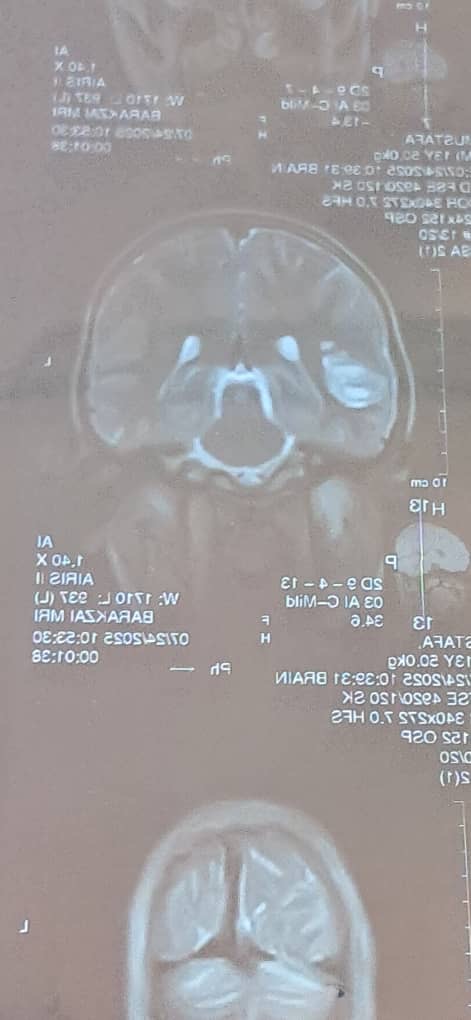

Hi my name is Rustam and I’m helping raise funds for my cousin in Afghanistan who is currently suffering from brain tissue damage.

He is only 13 years old and is the main breadwinner for his family, and he has 2 other sisters , a mother and a brother to look after.

Unfortunately, all the hospitals in Kabul has advised my cousin that he needs to travel to Pakistan or a foreign country to receive treatment, as they cannot treat it in Afghanistan due to the lack of specialists and resources in the country.

As a result my cousin and his family need to travel to Pakistan, Karachi and have to pay for private treatment. This will most likely cost them tens of thousands of pounds, including the price of Visas to travel to Pakistan and accommodation.

If my cousin does not get the help he needs, unfortunately his symptoms will get worse, eventually leading him having to have a permanent full time carer, being disabled, and potentially losing his life.